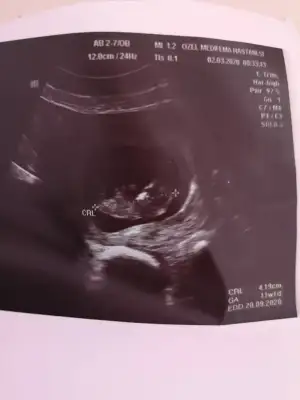

Buda net değil fotoyu cekerkenmi bozuluyor acaba

13 haftalikken bir doktor kız dedi 1 hafta sonra başka bir doktor erkek dedi 3 hafta sonra kız diyen doktor yine kız dedi ama hiçbiri net konuşmuyorHayırlısı çok net değil usg bakalım kızmı erkekmi şimdi kaç haftalık hamilesiniz dr ne zaman kız yada erkek dedi devaml gittiğiniz drmu kız yada erkek dedi

Bencede kız 2 defa kız demiş aynı dr13 haftalikken bir doktor kız dedi 1 hafta sonra başka bir doktor erkek dedi 3 hafta sonra kız diyen doktor yine kız dedi ama hiçbiri net konuşmuyor

Sanki kız gibi ama emin değilim nubu karanlık kalmış 12 yada 13 haftada paylaşın emin olmak istiyorum